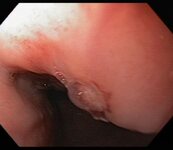

Large gastric ulcer with large, protuberant visible vessel

From the collection of Douglas G. Adler, MD